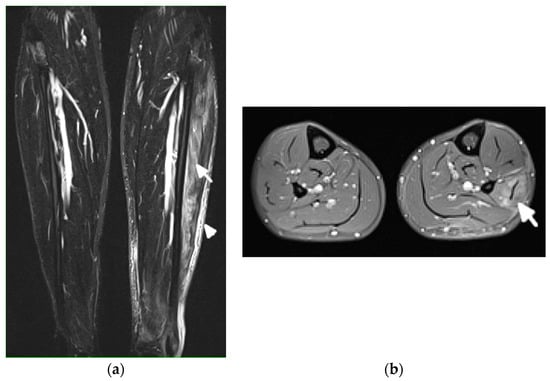

Figure 9.

Magnetic resonance (MR) imaging of lower legs of a 34-year-old male with systemic lupus erythematosus with myositis. (a) Coronal T2 turbo inversion recovery magnitude and (b) axial postcontrast T1-weighted MR images with fat saturation show increased signals in the muscles of the lower left leg (arrows), especially peroneus brevis and the lateral head of gastrocnemius, and to a lesser extent, soleus musculature, with heterogeneous enhancement in (b) after the administration of a gadolinium base contrast agent. In (a), note the subcutaneous edema around the left lower leg (arrowhead).